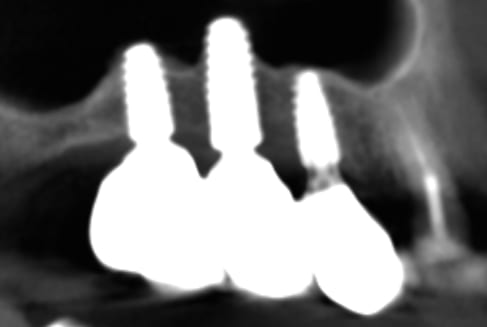

Case 1 (Figure 3 through Figure 24) depicts a 3-year follow-up of combined osseodensification sinus protocol IV in a severely resorbed maxillary ridge with ≤0.5 mm bone height in molar sites and horizontal deficiency at the first premolar site, using a two-stage approach for implant placement.

Case 2 (Figure 25 through Figure 36) illustrates a 3-year follow-up of the osseodensification sinus protocol IV in a severely resorbed right maxillary ridge with <0.5 mm bone height in molar sites, using a two-stage approach for implant placement.

Case 3 (Figure 37 through 44) shows a case of significant trauma history with a 3-year follow-up of the osseodensification sinus protocol IV in a severely resorbed right maxillary ridge with ≤0.5 mm bone height in molar sites, using a two-stage approach for implant placement.